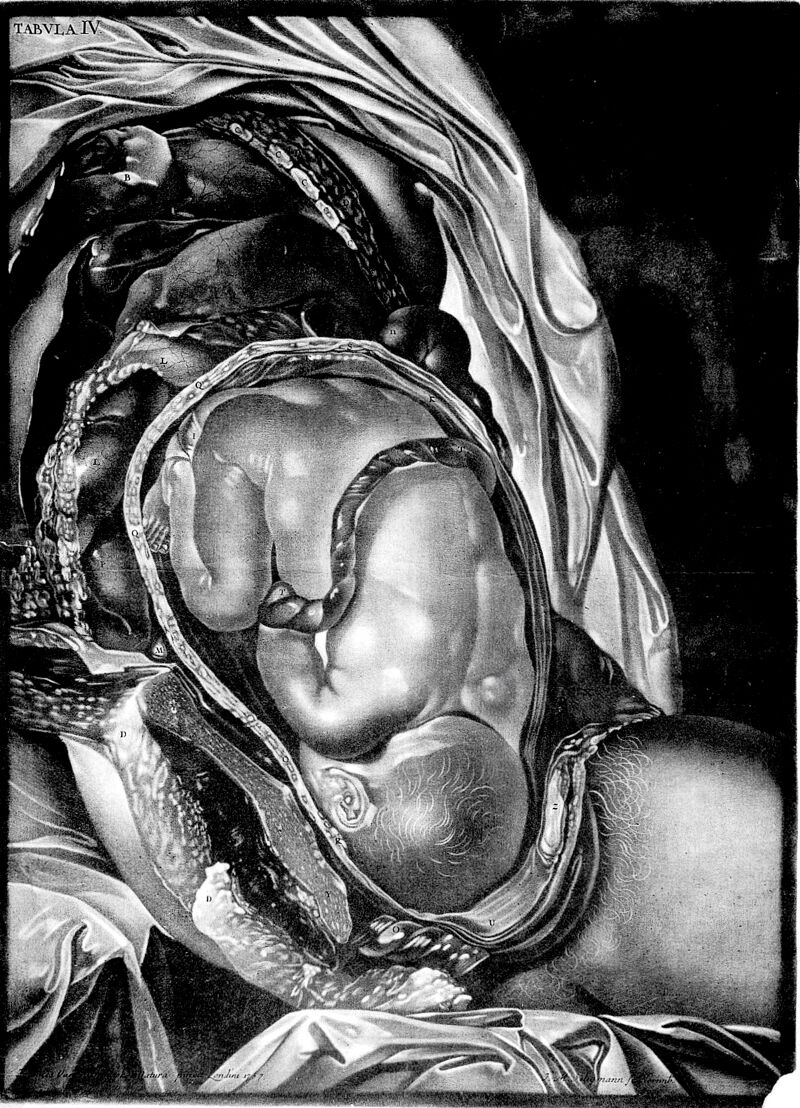

Demonstratio uteri praegnantis mulieris cum foetu ad partum maturi tabulis ... ea methodo dispositis, ut hujus status gravidi amplam ob oculos ideam collecent ... / Ad exemplar Londinense translata a D.C.C. Schmidel. In aes incisa .. a J.M. Seligmanno ... Abbildung der Gebähr-Mutter aus einer schwangern Frau, etc.

- Charles Nicholas Jenty

- 1761-1765

Credit: Demonstratio uteri praegnantis mulieris cum foetu ad partum maturi tabulis ... ea methodo dispositis, ut hujus status gravidi amplam ob oculos ideam collecent ... / Ad exemplar Londinense translata a D.C.C. Schmidel. In aes incisa .. a J.M. Seligmanno ... Abbildung der Gebähr-Mutter aus einer schwangern Frau, etc. Source: Wellcome Collection.